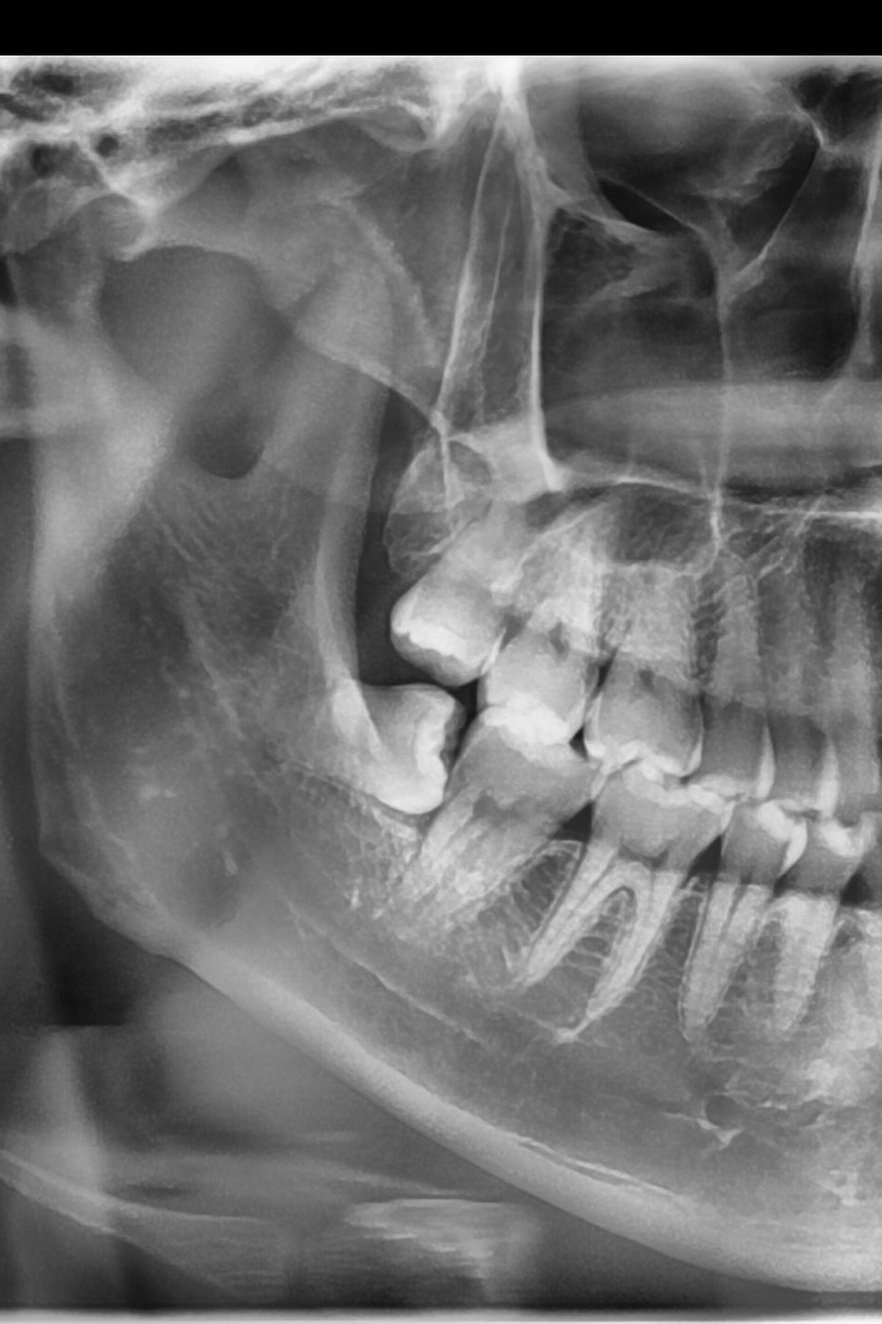

Horizontally impacted lower wisdom tooth with roots encasing the nerve — a high-risk case managed successfully without complications

Horizontally impacted lower wisdom tooth with roots close to the IAN.